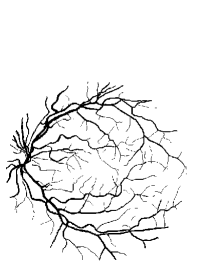

Refer to caption

Figure 5: Vessel skeleton extraction. (a) The green channel of the fundus image Igsubscript𝐼𝑔I_{g}. (b) The vessel enhanced image Iiuwsubscript𝐼𝑖𝑢𝑤I_{iuw}. (c) The binary image T𝑇T. (d) The background regions T1subscript𝑇1T_{1}. (e) The candidate regions T2subscript𝑇2T_{2}. (f) The vessel regions T3subscript𝑇3T_{3}. (g) T4subscript𝑇4T_{4}: The preserved regions in T2subscript𝑇2T_{2}. (h) The combined regions of T3subscript𝑇3T_{3} and T4subscript𝑇4T_{4}. (i) The vessel skeletons S𝑆S.

III-A2 Vessel Skeleton Extraction

Vessel Skeleton Extraction aims to further distinguish the unknown regions and provide more information on blood vessels. In Section V(B)-”Vessel Segmentation Performance”, the effectiveness of vessel skeleton extraction will be presented. Firstly, a binary image T𝑇T is obtained by global thresholding the enhanced vessel image Iiuwsubscript𝐼𝑖𝑢𝑤I_{iuw}.

T={1Iiuw>t0Iiuwt𝑇cases1subscript𝐼𝑖𝑢𝑤𝑡0subscript𝐼𝑖𝑢𝑤𝑡T=\left\{\begin{array}[]{rl}1&I_{iuw}>t\\ 0&I_{iuw}\leqslant t\end{array}\right. (8)

where t=Otsu(Iiuw)ε𝑡𝑂𝑡𝑠𝑢subscript𝐼𝑖𝑢𝑤𝜀t=Otsu(I_{iuw})-\varepsilon, ε𝜀\varepsilon is set as 0.030.030.03. Then T𝑇T is divided into three regions according to the Area𝐴𝑟𝑒𝑎Area feature:

T={T1if 0<Area<a1T2if a1Areaa2T3if a2<Area𝑇casessubscript𝑇1if 0<Area<a1subscript𝑇2if a1Areaa2subscript𝑇3if a2<AreaT=\left\{\begin{array}[]{rl}T_{1}&\text{if $0<Area<a_{1}$}\\ T_{2}&\text{if $a_{1}\leq Area\leq a_{2}$}\\ T_{3}&\text{if $a_{2}<Area$}\end{array}\right. (9)

In vessel skeleton extraction, the regions in T3subscript𝑇3T_{3} are preserved while the regions in T1subscript𝑇1T_{1} are abandoned. Then the regions in T2subscript𝑇2T_{2} with Extent>e2𝐸𝑥𝑡𝑒𝑛𝑡subscript𝑒2Extent>e_{2} && VRatior𝑉𝑅𝑎𝑡𝑖𝑜𝑟VRatio\leq r are preserved as T4subscript𝑇4T_{4}. Finally skeleton extraction [35] is performed on the combined regions of T3subscript𝑇3T_{3} and T4subscript𝑇4T_{4} in order to obtain the skeleton of blood vessels S𝑆S. An example of vessel skeleton extraction is shown in Fig.5.